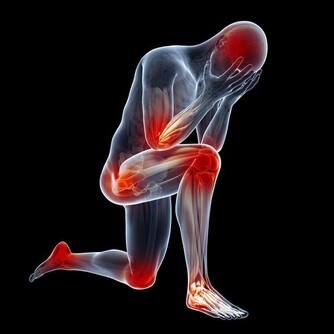

頸椎病患者更適合仰臥,這樣可以順應頸椎的生理彎曲,為達到枕頭支撐頸部的目的,患者最好將蕎麥皮枕頭的形狀稍加整理,使其形成一個中間凹、兩邊凸的形狀,高起的部分相當於自己的拳頭。睡眠時儘量枕著中間凹的部位,開始時不太習慣,經過長期適應,可以最大程度減少睡眠過程中的翻身動作。 蕎麥皮枕頭的適應性強,填充枕頭時,不要填得太滿,否則影響其塑形,填充約70%即可。(蘇玉梅)